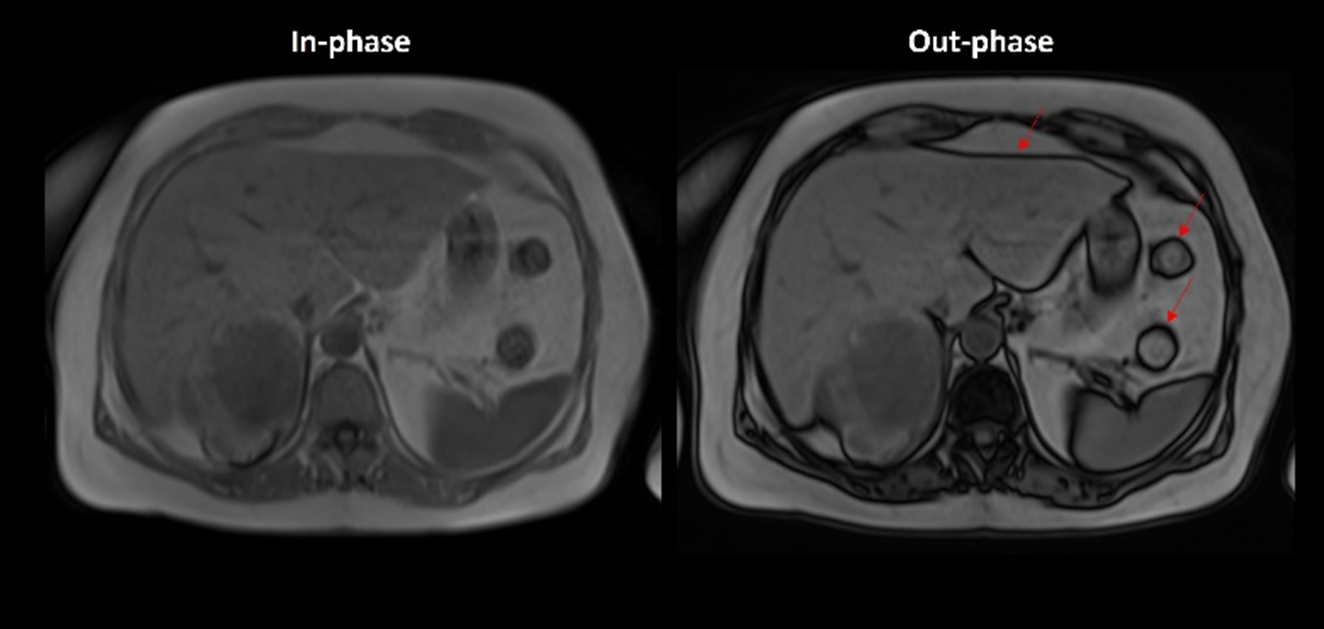

Σε αντίθεση με το τεχνικό σφάλμα χημικής μετατόπισης πρώτης τάξης, το οποίο οφείλεται στις διαφορές συχνότητας ανάμεσα στο νερό και...

Το συγκεκριμένο τεχνικό σφάλμα εμφανίζεται ως απώλεια σήματος ή ως ζώνες έλλειψης σήματος στις εικόνες. Η απώλεια σήματος συμβαίνει επειδή...

Πρόκειται για ένα τεχνικό σφάλμα που μπορεί να προκαλέσει σοβαρά διαγνωστικά προβλήματα στην απεικόνιση μαγνητικού συντονισμού. Οπτικά είναι εμφανές ως...